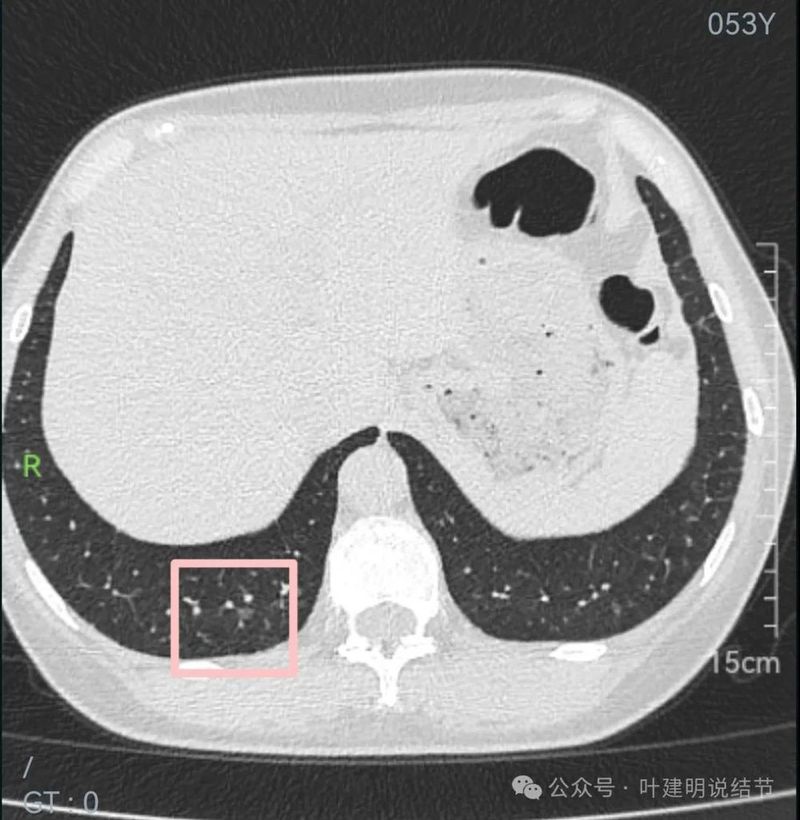

左下很淡也不太确切的磨玻璃影,轮廓与边界欠清。